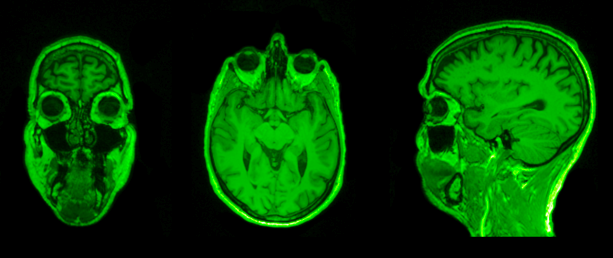

plan coronal

ou frontal

plan horizontal

plan sagittal

plan coronal

ou frontal

plan horizontal

plan sagittal